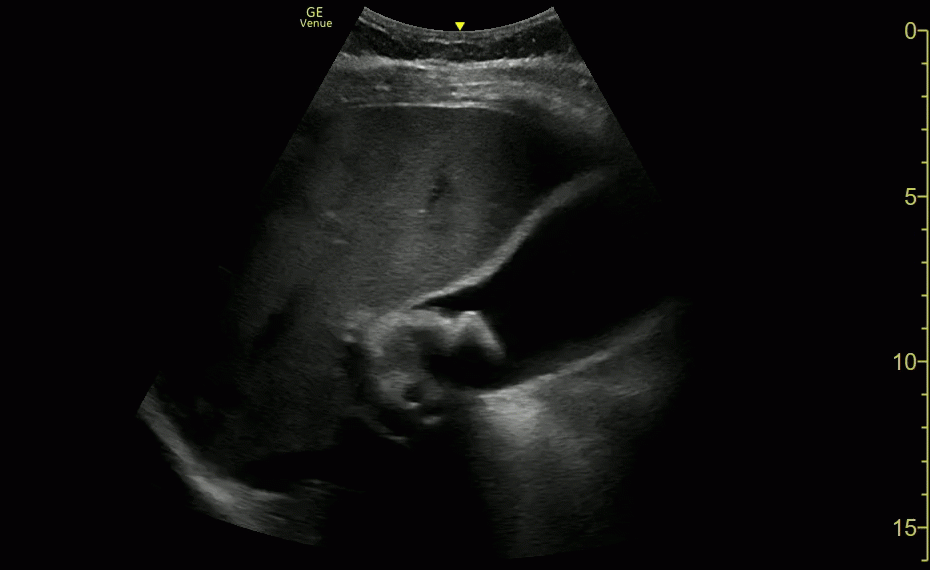

WES Sign (study 2)

WES Sign (study 1)